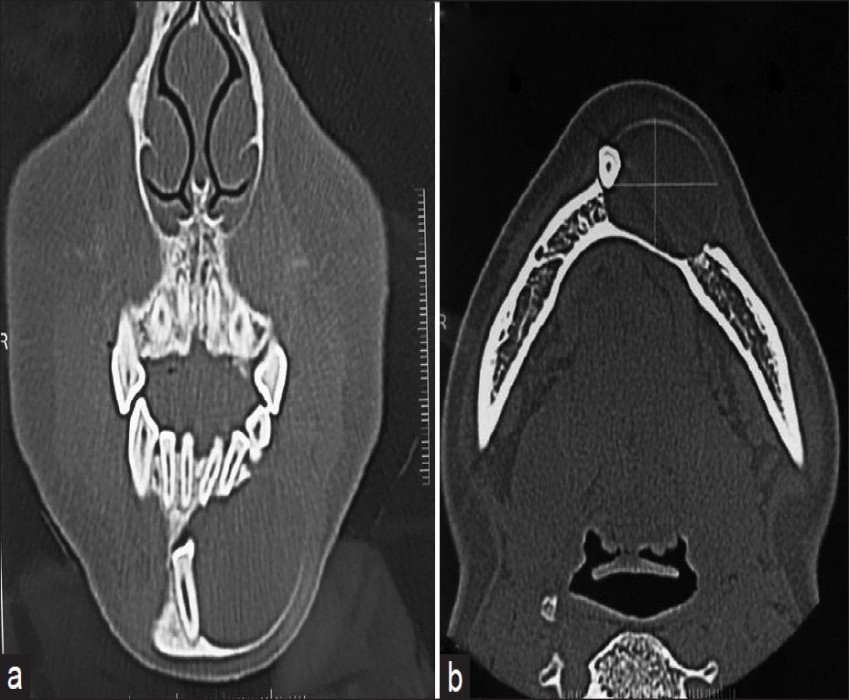

SURGICAL MANAGEMENT OF Maxillofacial Pathology: